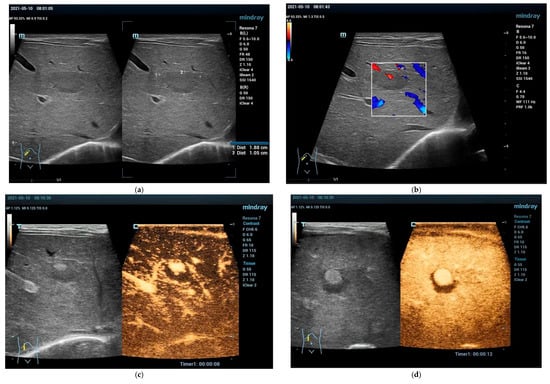

4.3.1. Hepatic Hemangioma

4.3.2. Congenital Hepatic Hemangioma

4.3.3. Infantile Hepatic Hemangioma

4.4. Vascular Malformations Other than Hemangioma

Focal Nodular Hyperplasia (FNH)